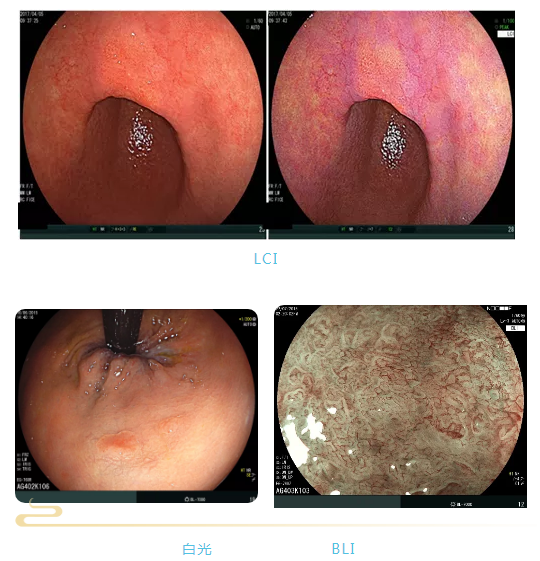

富士Eluxeo 7000 电子胃肠镜系统是利用多光源整合技术的新一代内窥系统,可实现白光及独家技术LCI、BLI多种观察模式,获得高对比的图像,观察粘膜表层微血管以及微结构。同时,Eluxeo 7000系统使用百万像素CMOS和HDTV输出,760放大内镜具有多段放大功能,对病变诊断更准确。

富士Eluxeo7000电子胃肠镜系统是先进的新一代内窥镜,能提高消化道早癌的诊疗准确性。该系统采用多光源整合技术,提供高对比度图像,助力早癌筛查和微创治疗,显著改善患者预后和生活质量。消化内镜医生致力于早癌的早发现、早诊断、早治疗,以拯救生命并减轻医疗负担。

富士Eluxeo7000电子胃肠镜系统是先进的新一代内窥镜,能提高消化道早癌的诊疗准确性。该系统采用多光源整合技术,提供高对比度图像,助力早癌筛查和微创治疗,显著改善患者预后和生活质量。消化内镜医生致力于早癌的早发现、早诊断、早治疗,以拯救生命并减轻医疗负担。